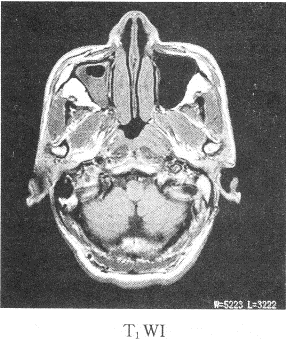

患者男性,39岁,因耳鸣,听力下降来院,影像学检查如图所示

1.该患者最有可能的诊断是

正确答案:1.C;2.B;3.ABDE 解题思路:鼻咽癌我国以广东省为高发地区,男性多于女性,好发于鼻咽顶壁,其次为侧壁,前壁和底壁极少。